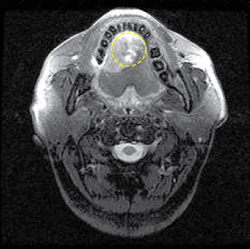

이 검사는 구강 내 연조직 특히 혀나, 윗 턱뼈, 근육 등으로 암이 침범하는 경우 전산화단층촬영 검사보다 진단에 조금 더 유용할 수 있습니다.

[자기공명영상]

혀에 발생한 암으로 병변의 크기를 자기공명영상(MRI) 사진을 통하여 선명하게 잘 알 수 있습니다.